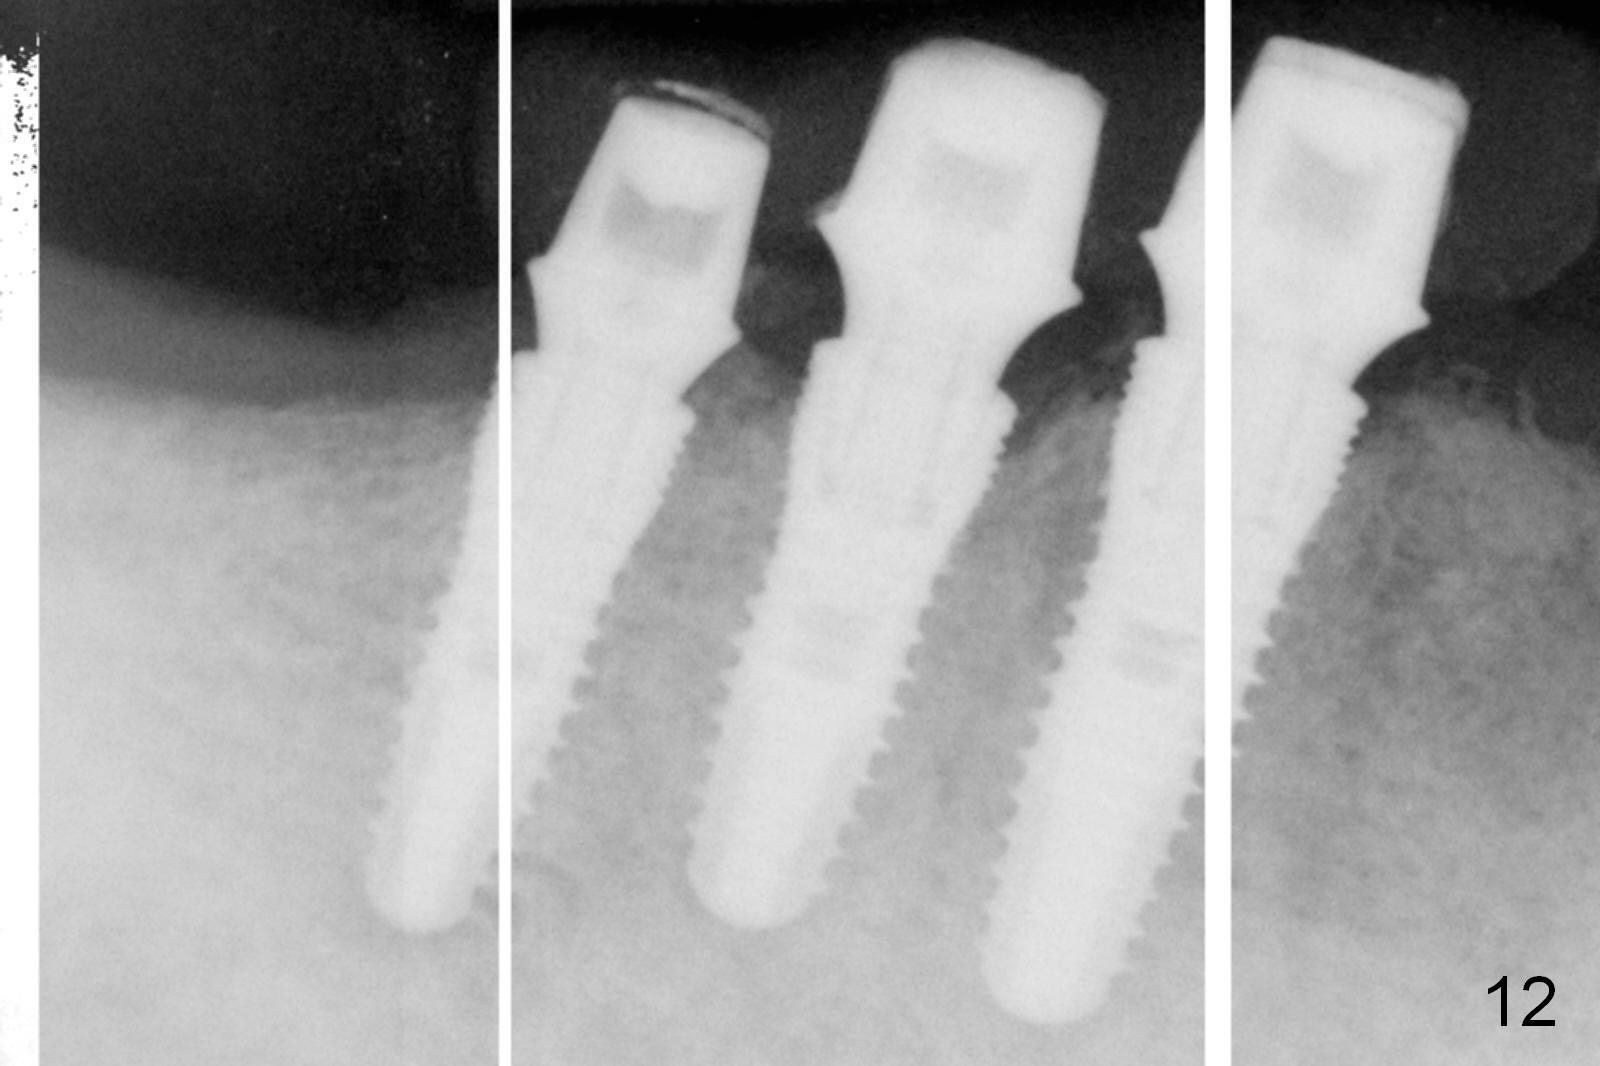

The patient returns for definitive restoration 5 months postop. There is no gross bone resorption around the implants (Fig.12). The surrounding gingiva is healthy (Fig.13). Since the edentulous space at #26 is relatively wide, one option is to splint #26-28 with #29 single. If the abutments at #27 and 28 are not parallel and the gingival margins are not at the same level too much, simply splint #26 and 27, since the implant at #27 is relatively long and wide.